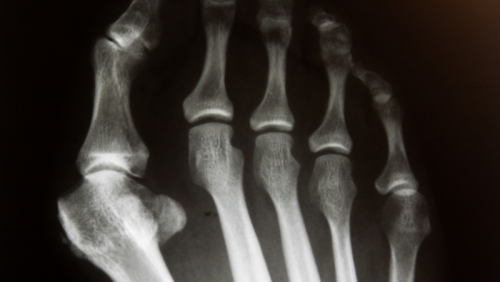

Des radiographies sont souvent nécessaires pour évaluer la gravité de la déformation, l'angle métatarsophalangien et d'éventuelles complications articulaires. Ces éléments contribuent à la classification de l'hallux valgus selon des critères spécifiques. La différenciation d'autres pathologies similaires est également cruciale. L'avocat spécialisé en responsabilité et expertise médicale doit comprendre ces procédures diagnostiques pour établir la base factuelle des litiges.